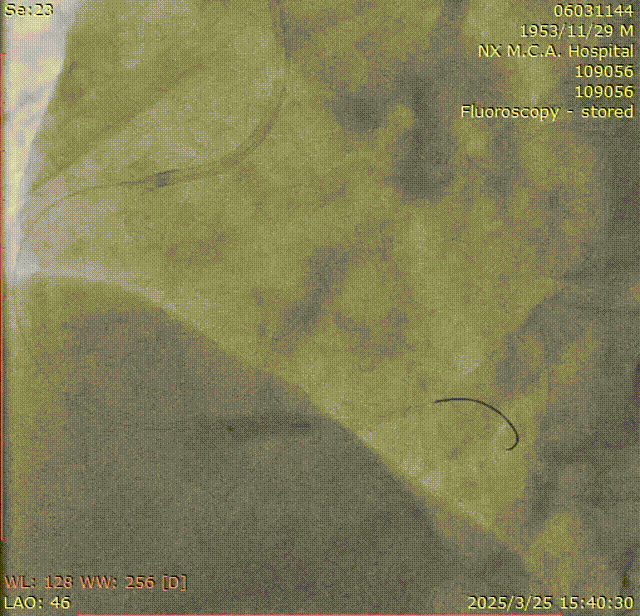

左图. 顺应性球囊:2.5mm*15mm

右图. 切割球囊:2.75mm*10mm

左图. 支架:3.0mm*13mm 14atm

中图. 支架:3.5mm*18mm 14atm

左图. NC:3.0mm*9mm- 16atm

右图. NC:3.75mm *12mm-16-18atm

最终结果